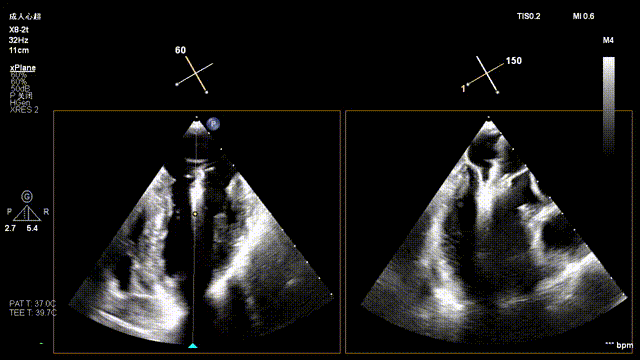

The operation was performed in a hybrid operating room and completed under the guidance of real-time three-dimensional transesophageal echocardiography (3D TEE) and X-ray fluoroscopy throughout the entire process.

Preoperative Imaging

Mitral regurgitation

Mitral valve Zone 2